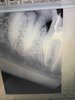

-Лечение к\к вертикальная конденсация гуттаперчей.

Хирургический протокол.Базовый курс по дентальной имплантации

Лектор Павленко М.Ю., Базовый курс по дентальной имплантации

Стоматология, Прогрессивная цифровая имплантология